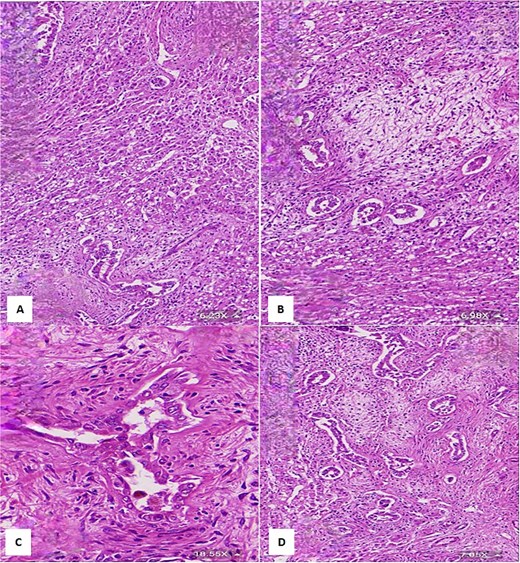

(A) Histological section showing interspersed islands of hepatocytes with retention of normal cell plate architecture (hematoxylin & eosin, 6.23×). (B) Myxoid area with benign duct structures and interspersed normal hepatocytes (hematoxylin & eosin, 6.98×). (C & D) Dilated and branching bile ducts show no cytological atypia (hematoxylin & eosin: C- 18.55×, D- 7.05×).